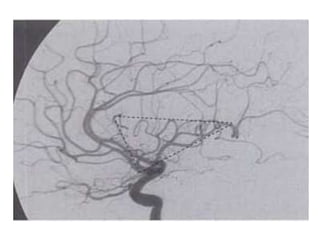

Sylvian triangle (angiographic)

• The superior insular line ( A line tangent to the

tops of the insular loops),

• Main MCA trunk ( forms the posterior inferior

margin of the triangle)

• Most anterior branch of the ascending frontal

complex ( forms the anterior border of the

triangle)

• It is seen in lateral view and serves as angiographic

landmark for localizing supratentorial masses.

• Round shift = Frontal lesion anterior to coronal

suture

• Square shift = Lesion behind foramen of Monro

in lower half of hemisphere

• Distal shift = Posterior to coronal suture in

upper half of hemisphere

• Proximal shift = Basifrontal lesion / anterior

middle cranial fossa including anterior temporal

lobe

Sylvian triangle (angiographic) •The superior insular line ( A line tangent to the tops of the insular loops), • Main MCA trunk ( forms the posterior inferior margin of the triangle) • Most anterior branch of the ascending frontal complex ( forms the anterior border of the triangle) • It is seen in lateral view and serves as angiographic landmark for localizing supratentorial masses.

• Round shift= Frontal lesion anterior to coronal suture • Square shift = Lesion behind foramen of Monro in lower half of hemisphere • Distal shift = Posterior to coronal suture in upper half of hemisphere • Proximal shift = Basifrontal lesion / anterior middle cranial fossa including anterior temporal lobe